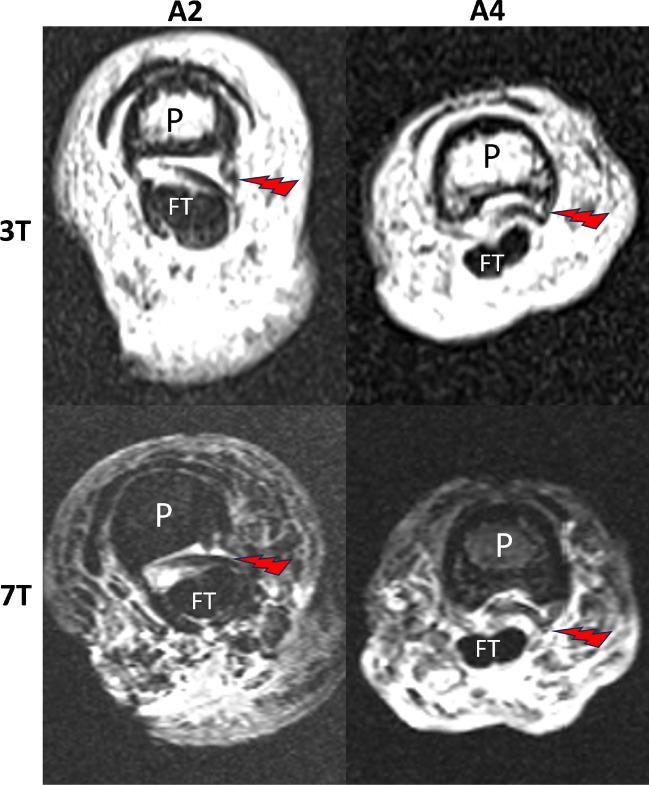

To compare image quality and diagnostic performance of 3T and 7T magnetic resonance imaging (MRI) for direct depiction of finger flexor pulleys A2, A3 and A4 before and after artificial pulley rupture in an ex-vivo model using anatomic preparation as reference.

30 fingers from 10 human cadavers were examined at 3T and 7T before and after being subjected to iatrogenic pulley rupture. MRI protocols were comparable in duration, both lasting less than 22 min. Two experienced radiologists evaluated the MRIs. Image quality was graded according to a 4-point Likert scale. Anatomic preparation was used as gold standard.

RESULTS

In comparison, 7T versus 3T had a sensitivity and specificity for the detection of A2, A3 and A4 pulley lesions with 100% vs. 95%, respectively 98% vs. 100%. In the assessment of A3 pulley lesions sensitivity of 7T was superior to 3T MRI (100% vs. 83%), whereas specificity was lower (95% vs. 100%). Image quality assessed before and after iatrogenic rupture was comparable with 2.74 for 7T and 2.61 for 3T. Visualization of the A3 finger flexor pulley before rupture creation was significantly better for 7 T (p < 0.001). Interobserver variability showed substantial agreement at 3T (κ = 0.80) and almost perfect agreement at 7T (κ = 0.90).

MRI at 3T allows a comparable diagnostic performance to 7T for direct visualization and characterization of finger flexor pulleys before and after rupture, with superiority of 7T MRI in the visualization of the normal A3 pulley.